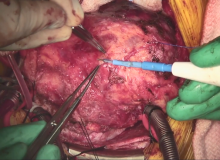

A repeat median sternotomy was performed and direct pressure measurement across the RVOT confirmed the preoperative gradient. CPB was then initiated via aortic and bicaval cannulation in the standard fashion. The authors proceeded to identify the LAD, which was quite challenging due to the mediastinal adhesions and the significant adherence of the left ventricular apex to the pericardium due to the previous apical incision. Using a combination of electrocautery at low settings and sharp dissection, the LAD was identified distally as it exited beyond the myocardium and was traced back to the intramyocardial segment. It was unroofed using Potts scissors and electrocautery.

In these cases, it is important to perform this procedure with the heart standstill to minimize risk of injury to the coronary artery, and it is also important to be precise with the direction of unroofing to avoid inadvertent entry into any ventricular cavity. The entire myocardial segment has to be unroofed. Sometimes the authors are faced with epicardial veins that needs to be clipped or divided. They administered a test dose of cardioplegia to ensure no significant bleeding from the myocardium, epicardial veins, or the unroofed coronary artery prior to removal of the aortic cross clamp. Once the unroofing was completed, attention was directed to the right ventricular outflow tract. The RV septal myectomy is a bit different from standard left ventricular myectomy.